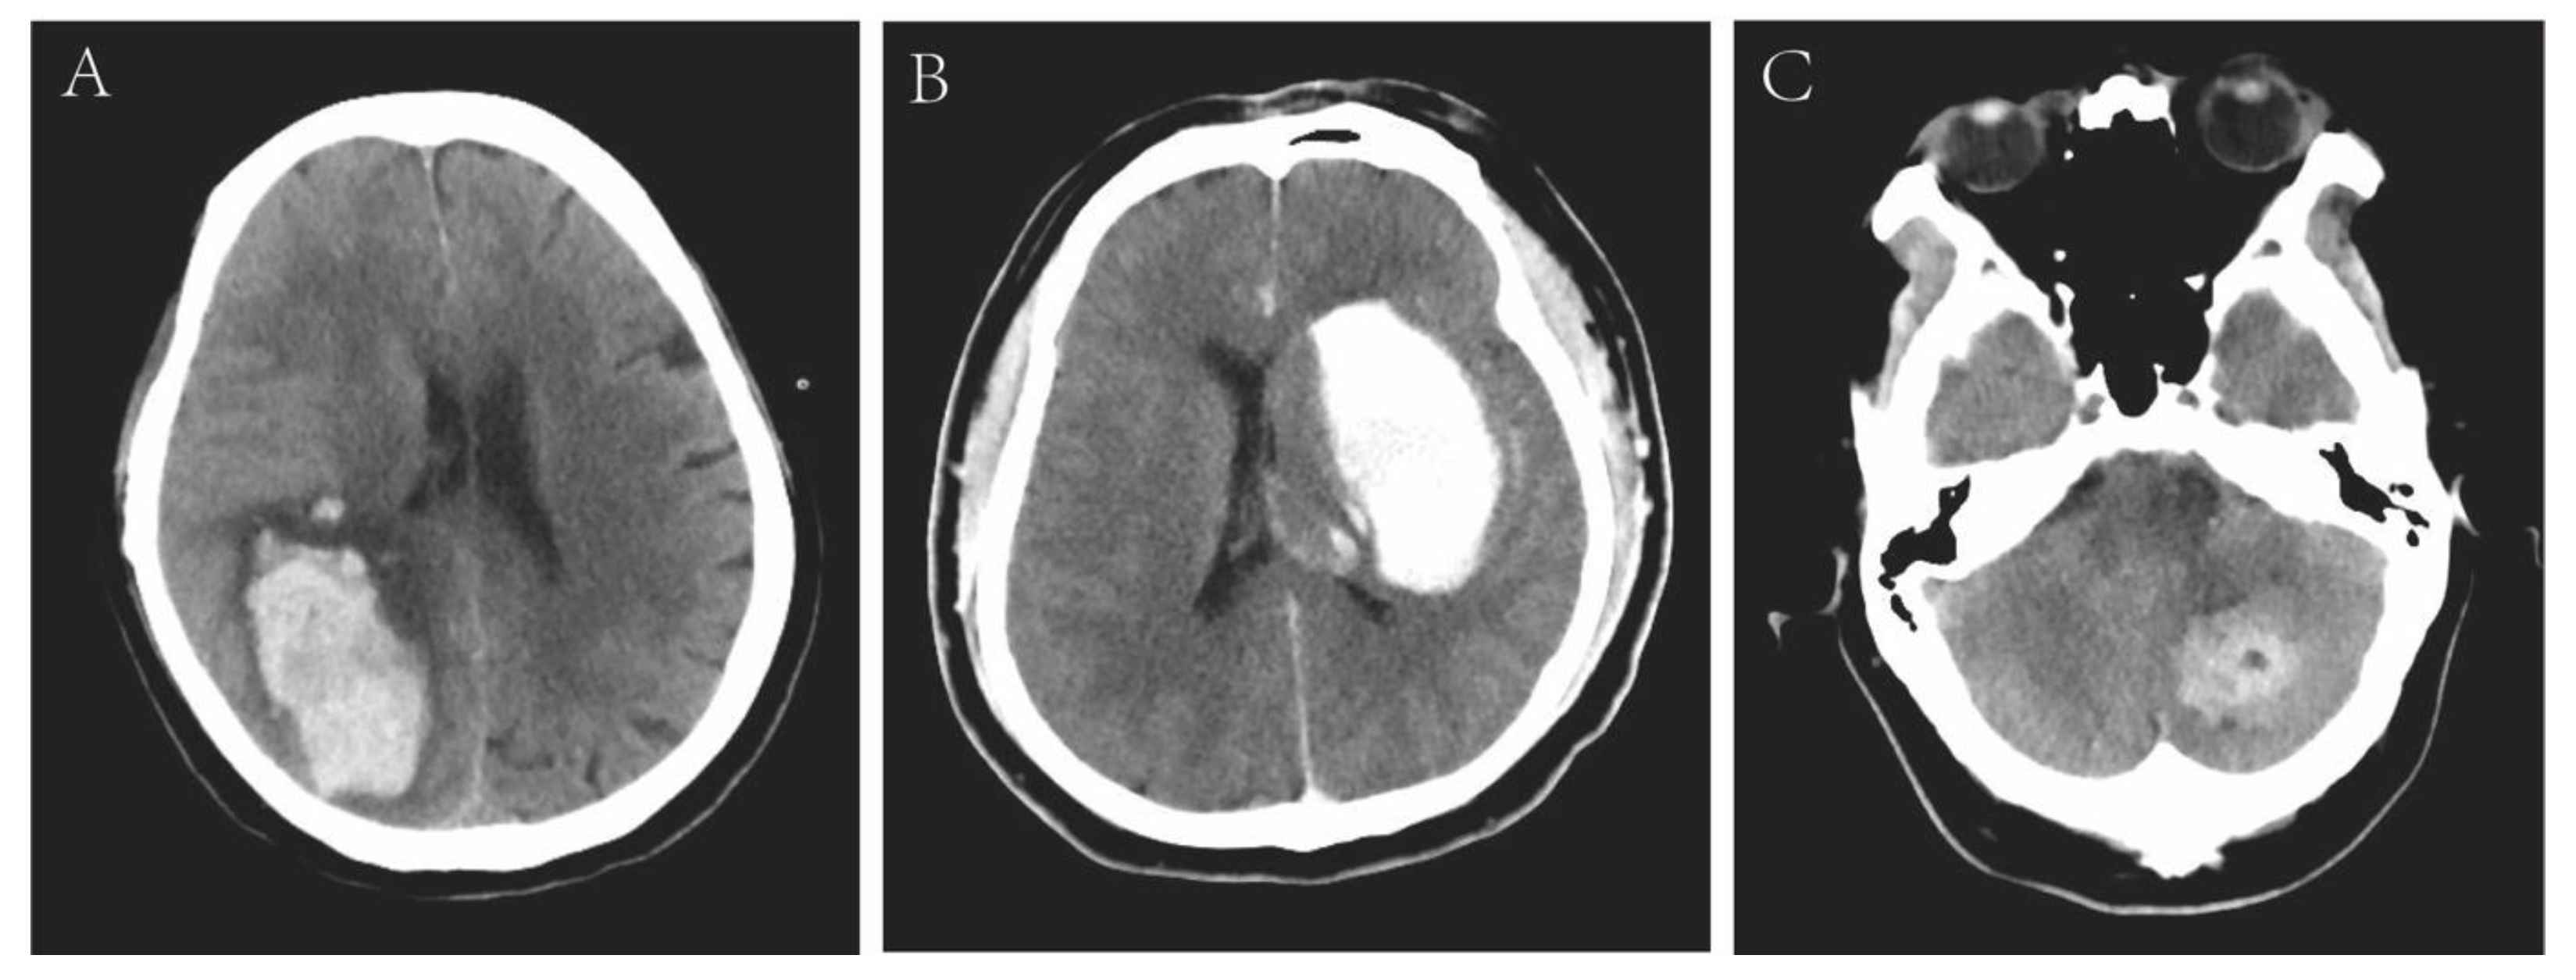

3.2. Imaging Characteristics

| Neuroradiologic data | ||||

| Location 1 | 0.109 | |||

| Lobar | 12 (66.7) | 10 (76.9) | 2 (40.0) | |

| Cerebellar | 4 (22.2) | 1 (7.7) | 3 (60.0) | |

| Deep (basal ganglia and thalamus) | 2 (11.1) | 2 (15.4) | 0 (0) | |

| Location 2 | 0.044 | |||

| Infratentorial | 4 (22.2) | 1 (7.7) | 3 (60.0) | |

| Supratentorial | 14 (77.8) | 12 (92.3) | 2 (40.0) | |

| Combined with SAH | 4 (22.2) | 4 (30.8) | 0 (0) | 0.278 |

| ICH volume, cm3 | 65.83 ± 53.34 | 84.17 ± 50.74 | 18.14 ± 20.85 | 0.001 |

| Small (<30 cm3) | 5 (27.8) | 1 (7.7) | 4 (80.0) | 0.008 |

| Large (≥30 cm3) | 13 (72.2) | 12 (92.3) | 1 (20.0) | 0.008 |

| Brain herniation | 4 (22.2) | 4 (30.8) | 0 (0) | 0.278 |

| Intraventricular hemorrhage | 2 (11.1) | 2 (15.4) | 0 (0) | 1 |

| Midline shift ≥ 10 mm | 6 (33.3) | 6 (46.2) | 0 (0) | 0.114 |